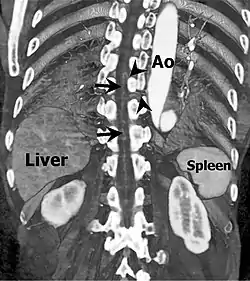

Coronal slab volume rendering image of CT aortography shows artery of Adamkiewicz entering spinal canal(arrowheads) and joining the anterior spinal artery (arrows) after a hairpin turn.